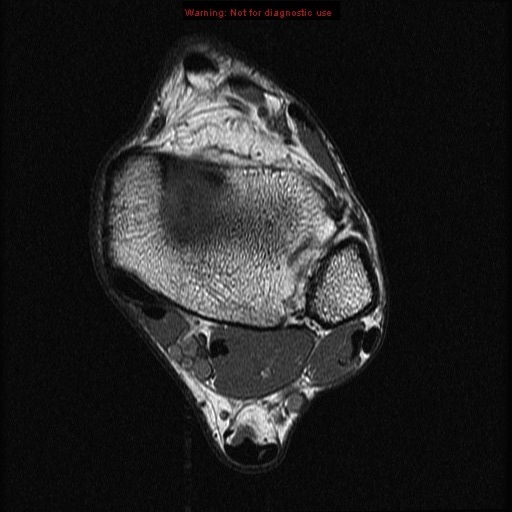

Stanford MSK MRI Atlas

middle subtalar joint

tibiotalar joint

posterior subtalar joint

achilles tendon

calcaneus

calcaneus lateral process of the talus

body of talus